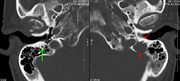

A CT of the brain revealed a lytic lesion in the left temporal bone (right side of image), and petrous temporal bones involving the mastoid segment of the facial nerve canal. Red arrows: lesion; green arrow: normal contralateral facial nerve canal. The lesions are consistent with a myeloma deposit.